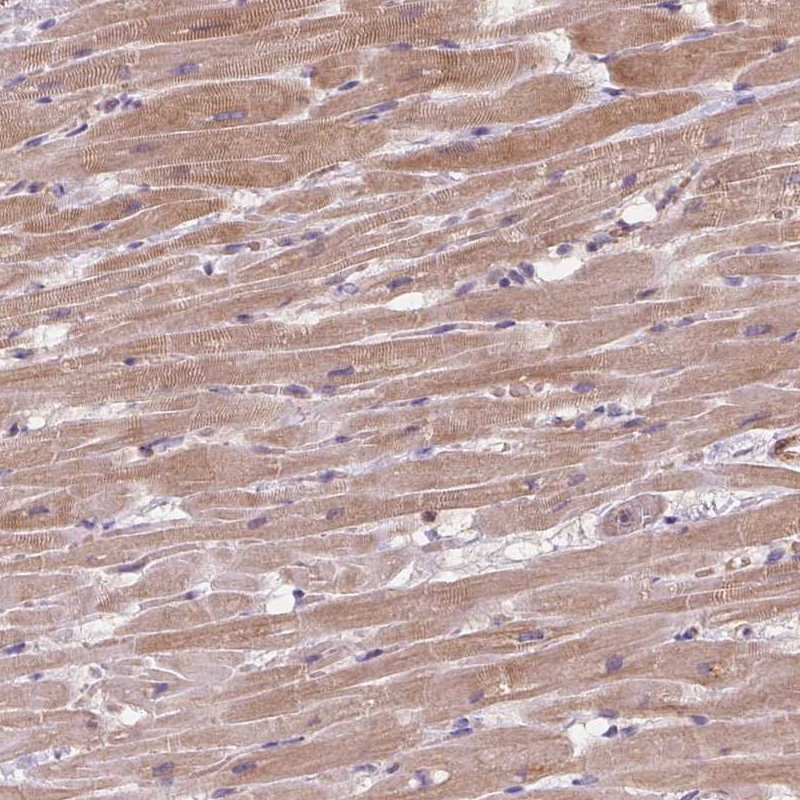

Immunohistochemical staining of human heart muscle shows moderate cytoplasmic positivity in myocytes.